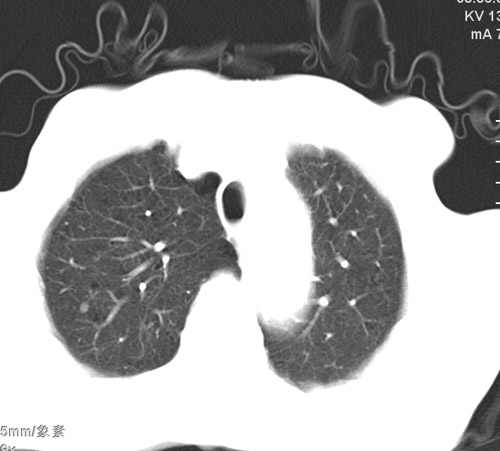

标题: CT17529:男 76 胸背部不适半月 胸透支气管炎 行CT检查 [打印本页]

标题: CT17529:男 76 胸背部不适半月 胸透支气管炎 行CT检查

意见 老年肺 少许炎症 肺大泡 右肺门略大 但支气管通畅  请各位高手指教如何下意见

间质纤维化伴少许炎症!另:肺大泡形成!

支持楼主意见,右肺门略大,可能为肺动脉增粗.